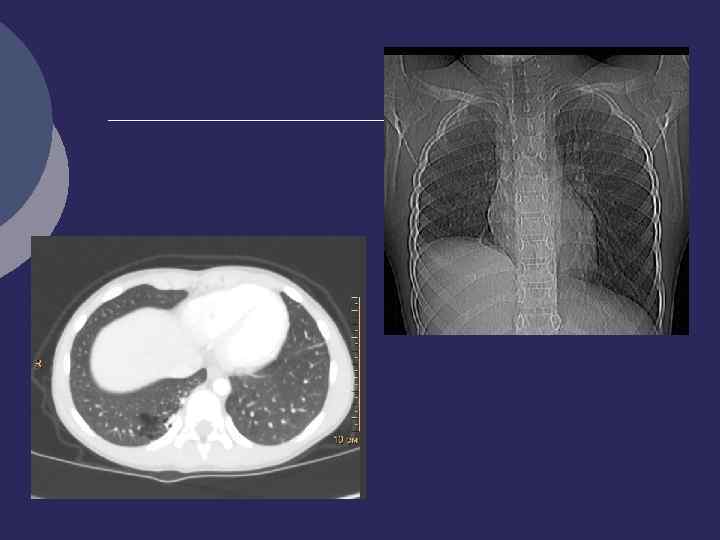

Внутрилегочная секвестрация